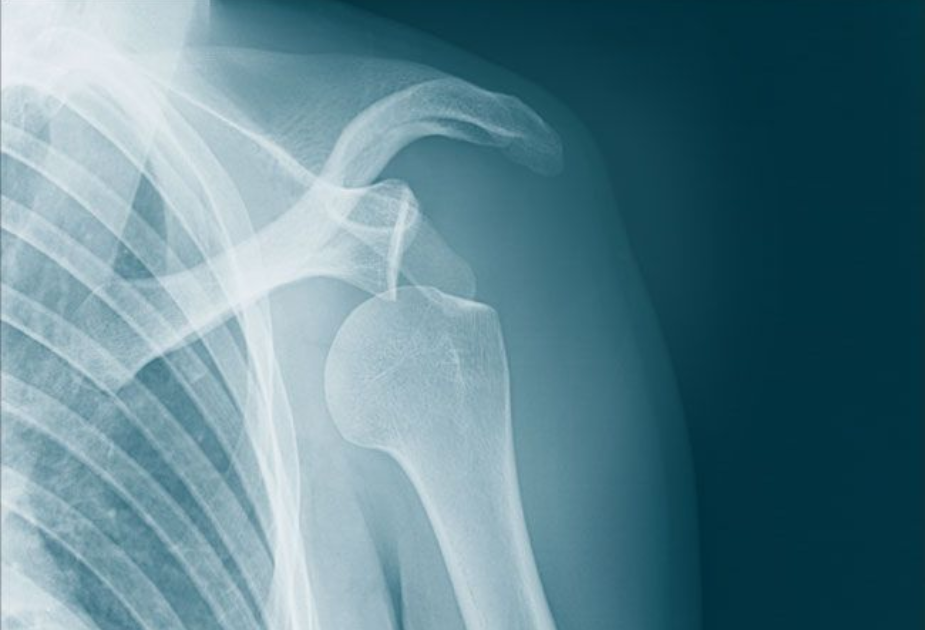

Recurrant shoulder dislocation

The shoulder is the most mobile joint in the human body, allowing a wide range of movements such as lifting, rotating, and reaching. However, this high degree of mobility also makes it vulnerable to instability and dislocation. When a shoulder dislocation occurs repeatedly — even after the first incident — it is referred to as recurrent shoulder dislocation.

A recurrent shoulder dislocation happens when the shoulder joint repeatedly slips out of its socket (the glenoid). This typically occurs after a first-time traumatic dislocation, especially if the soft tissues or ligaments around the shoulder fail to heal properly. Once the shoulder becomes unstable, even small movements or minor trauma can cause another dislocation.

• Hill-Sachs lesion: A dent or bone defect in the humeral head caused by impact during dislocation can lead to repeated instability.

• X-rays: To detect bone damage or defects.